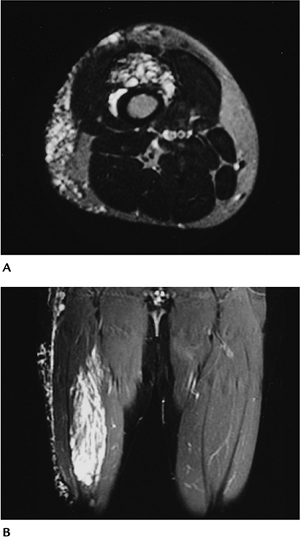

FIGURE 10-46 Hemangioma. (A) Axial T2-weighted and (B)

coronal gradient echo MR images demonstrating deep and superficial hemangiomas in the distal thigh with markedly increased signal intensity in serpiginous vascular structures. |